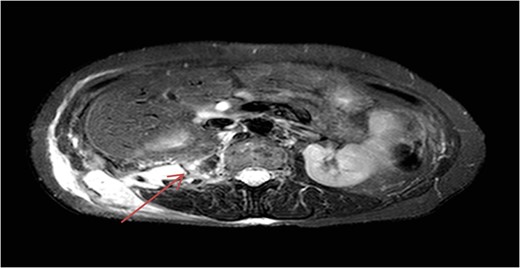

MRI of abdomen showing right retroperitoneal collection extending into right flank.

Her symptoms had been managed conservatively until re-presenting 3 years later with a back (lumbar) lump. Due to the uncertainty over the nature of this back lump, a CT and magnetic resonance image (MRI) of the abdomen was carried out. This revealed an abnormal 6.2 × 3.1 × 11.4 cm3 retroperitoneal collection extending from the posterior right edge of the liver until passing through the abdominal wall to form the palpable mass in the right flank (Figs 1 and 2).